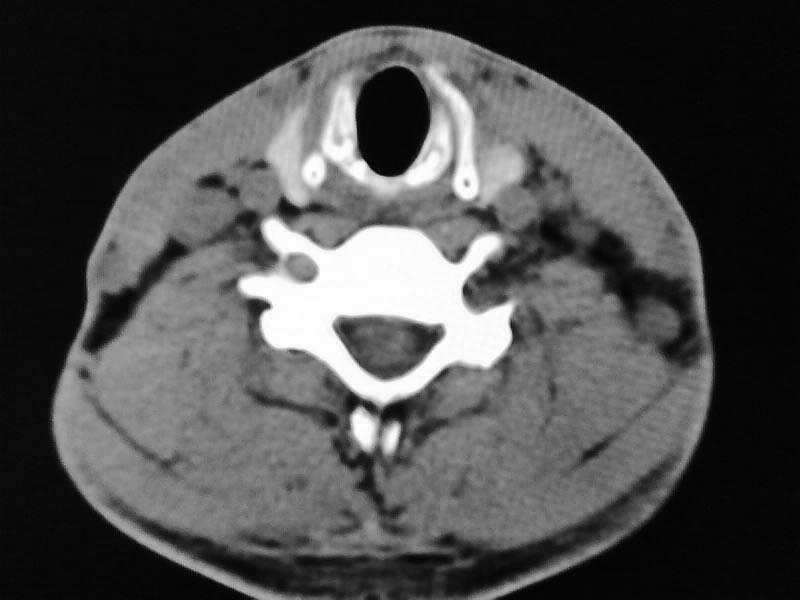

以下是引用余辉在2009-5-3 11:36:00的发言:[br]左侧胸锁乳突肌下方不规则肿物影,边界不清,内部密度不均,左侧颈外侧区脂肪增多,多发淋巴结肿大,考虑淋巴或神经来源肿瘤可能性大,不除外淋巴结炎,肌源性肿瘤及增生性肌炎等,活检